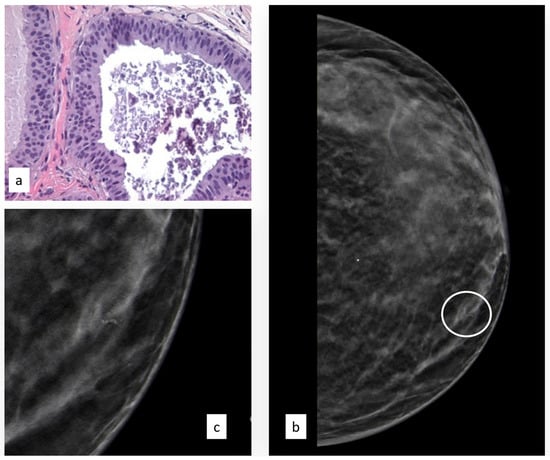

The initial radiological findings were 82 microcalcifications, 28 masses, and two architectural distortions; the mean radiological suspicion level was BIRADS 3 (range 3–5). Illustrative radiologic and histologic examples of FEA are shown in Figure 3.

Figure 3.

Histologic picture (a, Magnification (×20)) and radiological presentation ((b) left CC view; (c) magnification) of flat epithelial atypia (white circle).

Of the 112 FEA patients, 8 (7.3%) developed subsequent breast cancer during follow-up, 2 (25%) in the same breast as the FEA and 6 (75%) in the contralateral breast.

The median time interval from first diagnosis of a B3 lesion to subsequent diagnosis of BC was 53.5 months.

The initial radiological findings were 114 microcalcifications, 84 masses, and two architectural distortions; the mean radiological suspicion level was BIRADS 4 (range 3–5). Illustrative radiologic and histologic examples of ADH are shown in Figure 4.

Figure 4.

Histologic picture (a, Magnification (×20)) and radiological presentation ((b) right MLO view; (c) magnification) of atypical ductal hyperplasia (white circle).

Of the 200 ADH patients, 27 (13.6%) developed subsequent breast cancer during follow-up, 18 (66.6%) in the same breast as the ADH and 9 (33.3%) in the contralateral breast.

The median time interval from first diagnosis of a B3 lesion to subsequent diagnosis of BC was 32 months.